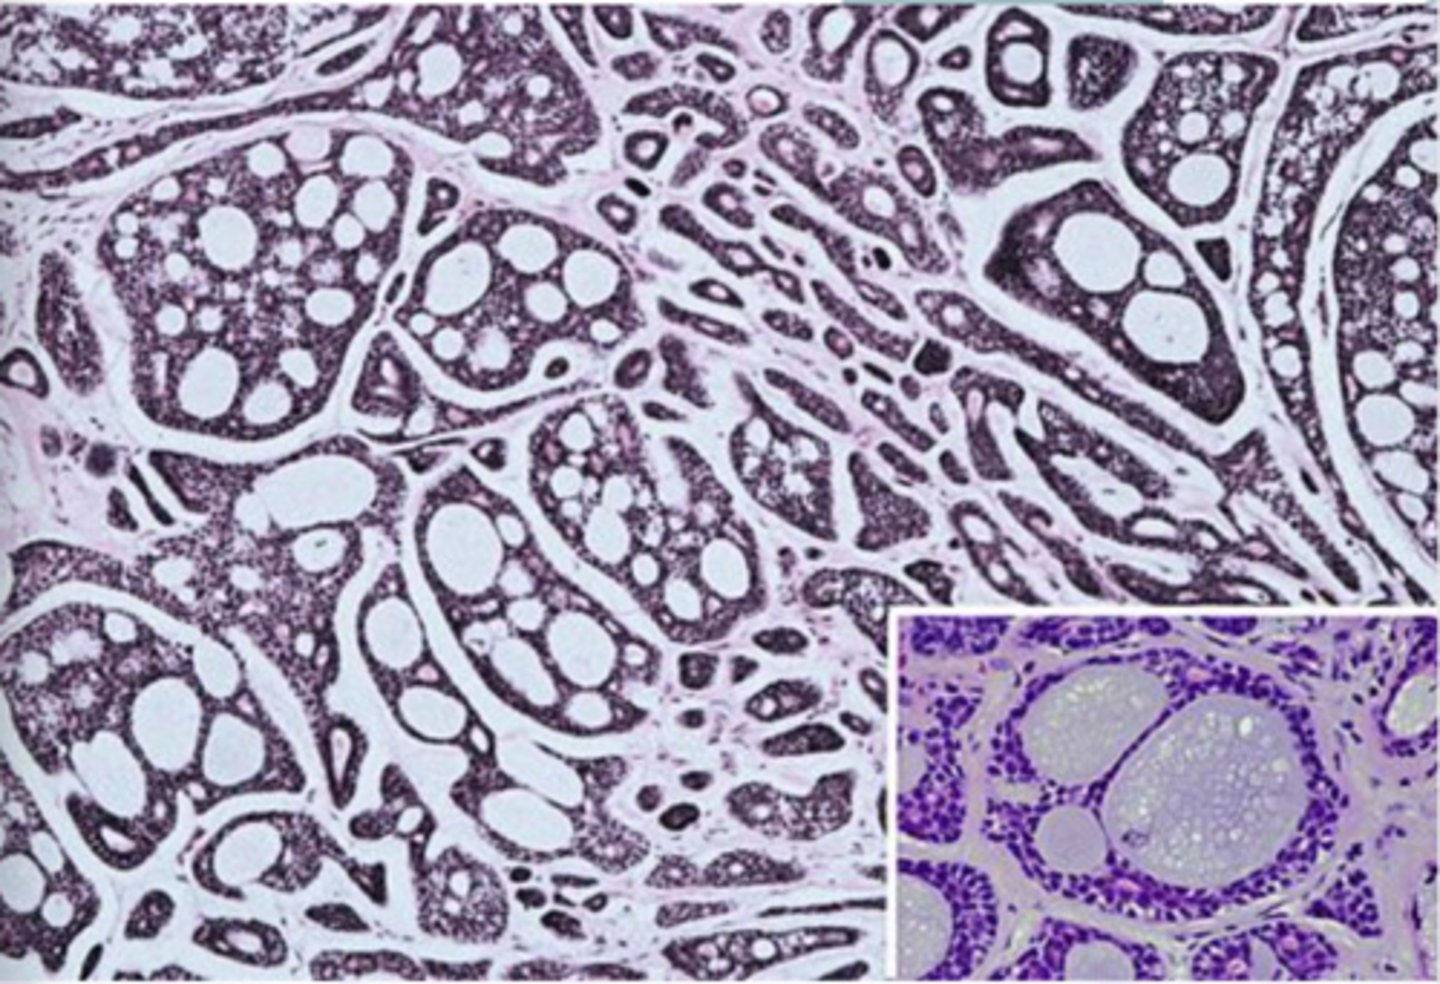

Warthin Tumor

-Cyst lined by uniform rows of oncocytic cells

-The lining is papillary in appearance

-The cyst wall is composed of abundant lymphocytes

6-12%

Warthin tumor has what percent recurrence after surgical removal?